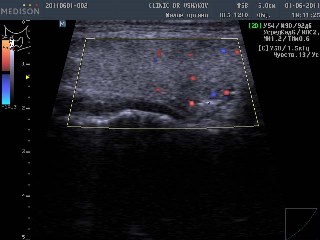

| В левой доле (в сосудистом режиме; ЦДК) заметна умеренная интенсификация кровотока ― свойственно избыточному напряжению железы |

В левой доле (в сосудистом режиме; ЦДК) кровоток восстановился до оптимальной интенсивности ― характерно тоническому (нормальному) состоянию железы |